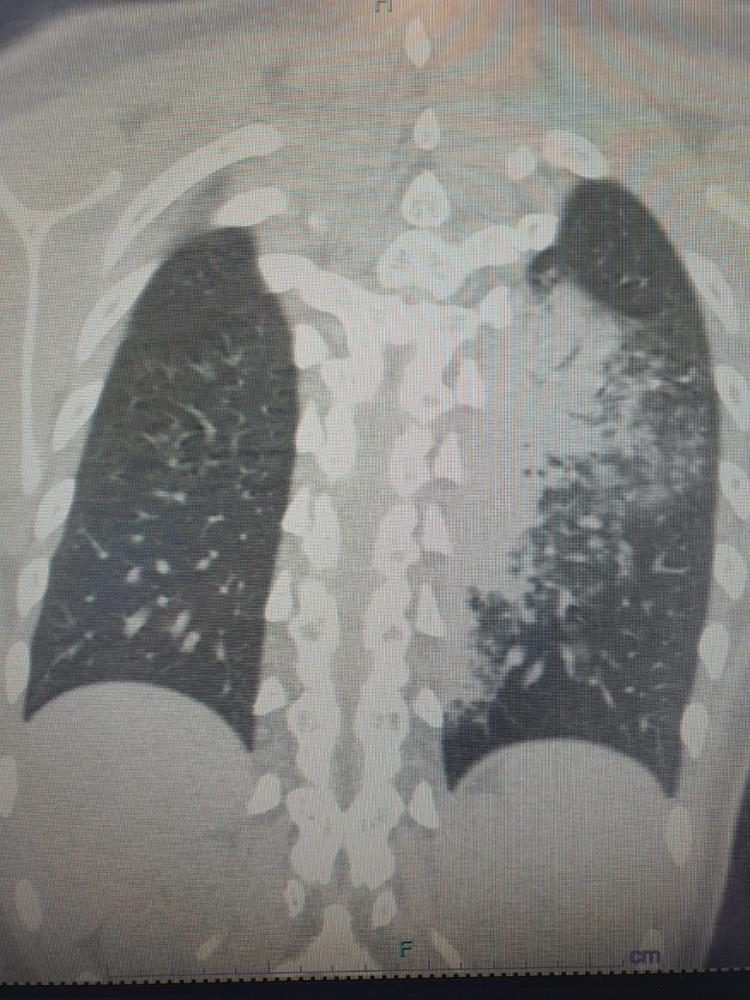

Göğüs Hastalıkları Uzmanı Prof. Dr. Şevket Özkaya, özellikle otel ve tatil köylerinde konaklayan kişiler arasında “beni klima çarptı” diyen neredeyse her iki kişiden birinde bu hastalıkların saptandığını belirtti. Prof. Dr. Özkaya, bu durumdan en çok etkilenenlerin ise çocuk yaş grubu olduğunu vurgulayarak, “Ciddi sayıda, daha önce görülmemiş derecede çocuk bronşiti ve zatürresi vakaları görmeye başladık. Hatta COVID-19 salgınında, çocuk yaş grubunda COVID-19 virüsüne bağlı bu kadar çok zatürre görmüyorduk. Son günlerde; ‘Legionella’ bakterisinin, çocuk yaş grubunda COVID-19’a oranla çok daha fazla zatürreye neden olduğunu görüyoruz” diye konuştu.